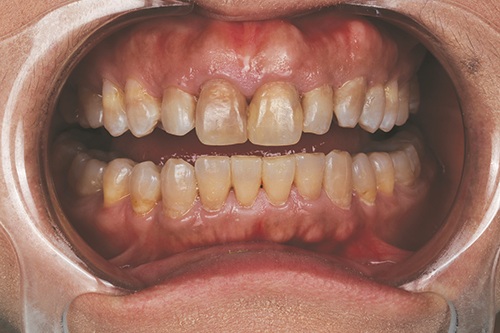

Advancements in digital manufacturing have enabled the fabrication of highly precise, ultra-thin restorations that minimize or eliminate the need for tooth reduction. This case report describes the aesthetic management of a 49-year-old patient with severe tetracycline staining (Figs. 1–3), using a no-prep approach and 3D-printed zirconia veneers. A fully digital workflow was employed, including intraoral scanning, virtual smile design (Fig. 4), and additive fabrication of 120-µm (0.12mm) zirconia shells (Figs. 5–7), to achieve a conservative aesthetic outcome while preserving natural tooth structure.

Fig. 3

The patient presented with concerns of long-standing, generalized tooth discoloration. Despite multiple previous attempts with both at-home and in-office bleaching treatments, there was no significant improvement in the tetracycline staining resulting from prior antibiotic exposure.

Discoloration caused by tetracycline exposure from childhood. The patient was happy with her smile and the natural shape of her teeth, but desired a conservative solution to lighten the color of her “dark teeth.”

Radiographic and clinical exams revealed no active carious lesions or infections. The patient has a history of restorative work, including a combination of composite and amalgam fillings. The patient had previously completed orthodontic therapy and has a Class I occlusion. No signs of clenching or bruxism were observed.

Intrinsic discoloration induced by tetracycline.

The patient presented with generalized intrinsic discoloration consistent with moderate to severe tetracycline staining, characterized by grayish-brown horizontal banding across the anterior dentition. Given the etiology of tetracycline-induced staining, originating from deep within the dentin and enamel matrix, conventional whitening treatments are typically insufficient for achieving satisfactory aesthetic outcomes. The patient’s primary objectives were to enhance the aesthetic appearance of her smile, preserve natural tooth structure, and maintain flexibility for potential revision in the future. To address these goals, 3D-printed zirconia veneers were selected as a minimally invasive option with masking characteristics suitable for intrinsic discoloration.